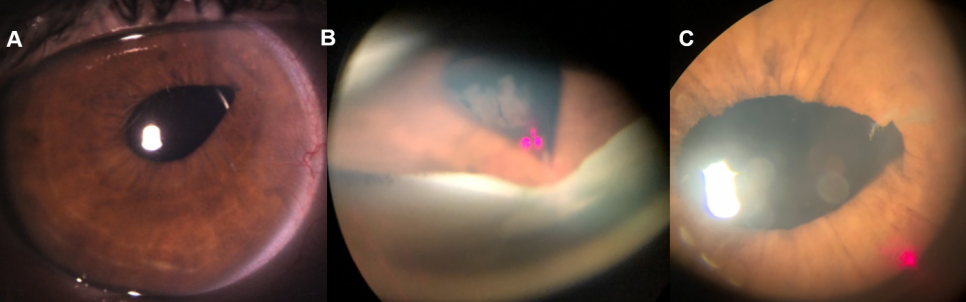

그림 1. (A)테논난하트리암시놀론(Sub-Tenon Triamcinolone) 주입술, (B) 주사 전 CME, (C) 주사 2개월 후 호전-중심 오목 형태가 유지 중 ④ 유리체강 내 주사 ⑤ 트리암시놀론(Triamcinolone, 그림 2-A) : 혈액망막 장벽(Blood Retinal Barrier; BRB) 파괴를 감소시킵니다.* 재발성 CME에 유용하지만 효과가 일시적이기 때문에 일정 기간이 지나면 재발합니다. →효과를 유지하기 위해서는 여러 번 주사를 맞아야 합니다.㉡ 덱사메타손 삽입물(Dextamethasoneimplant; Ozurdex®, 그림2-B&C): 보다 효과가 오래 유지되지만 여전히 재발로부터 자유롭지 못합니다.

그림2.(A) 유리체강내 트리엄시놀론주입, (B)덱사메타손삽입술장면, (C)삽입된 덱사메타손인플랜트(오더덱스)의 유리체강내 모습

그림 3.(A) 주사 전 CME, (B) 덱사메타손 플랜트 삽입술 후 6개월 – 호전된 CME ᅥᆫ시 投与 전신 투여 – 먹는 약 또는 정맥 주사 : 부작용 위험이 크므로 주의하십시오.

그림 5. (A)절개창에 끼워져 있는 유리체(Vitreous incarceration, Vitreous winksyndrome), (B)야그레이저 광원에 끼워져 있는 절개창을 조준하였으며, (C)야그레이저 조사 후 절개창에 끼워져 있던 유리체는 풀렸습니다.2) 유리체절제술(그림6) ① 절개창(창상) 내 또는 홍채와의 유착된 유리체 제거 ② 기존 유리체 제거 → 염증매개물질이 포함되어 있던 유리체를 제거함으로써 염증반응 감소 + 눈 깊은 내부로 약물 침투를 좋게 할 수 있습니다.③ 수술은 CME가 2개월 이상 지속됐을 때 시도해 볼 수 있지만 수술 자체가 가진 위험성과 수술 후에도 시력 호전이 없을 수도 있다는 사실을 반드시 환자에게 충분히 설명해야 합니다.